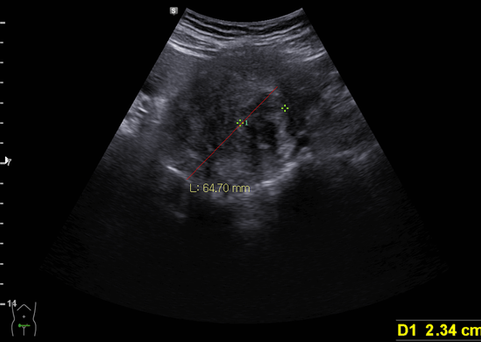

복부 초음파상 자궁근종/자궁선근증 관찰됨

; 평소 생리가 많은 날 외출하기 어렵고 패드가 흥건히 젖을 정도의 생리과다(menorrhagia)에 인한 반복되는 철결핍성 빈혈, 종괴 효과로 인한 방광 압박으로 소변 긴박 증상을 설명함.